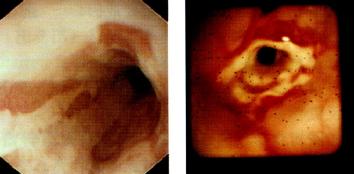

内镜(图3.15)

为诊断食管炎的金标准,既可对食管炎进行观察和分型,又可行食管粘膜活检。

以下为Savary和Miller制定的食管炎内镜下分型:

. Ⅰ期:单个或多个纵行非融合的红斑性粘膜损害,常覆有渗出物,发生于胃食和连接处上方或由连接处延伸开来

. Ⅱ期:融合性糜烂和渗出性粘膜损害,但并未累及食管全周

. Ⅲ期:全周性糜烂及渗出病变,覆盖整个食管粘膜

. Ⅳ期:慢性粘膜损害,如伴或不伴狭窄的溃疡。

图3.15食管远端内镜所见。(a)线状充血糜烂:反流性食管炎。图取自

Cotton & Williams,Practical Gastrointestinal Endoscopy,3rd edn,

1990(Blackwell Science,Oxford),经作者许可。(b)消化性食管狭窄。